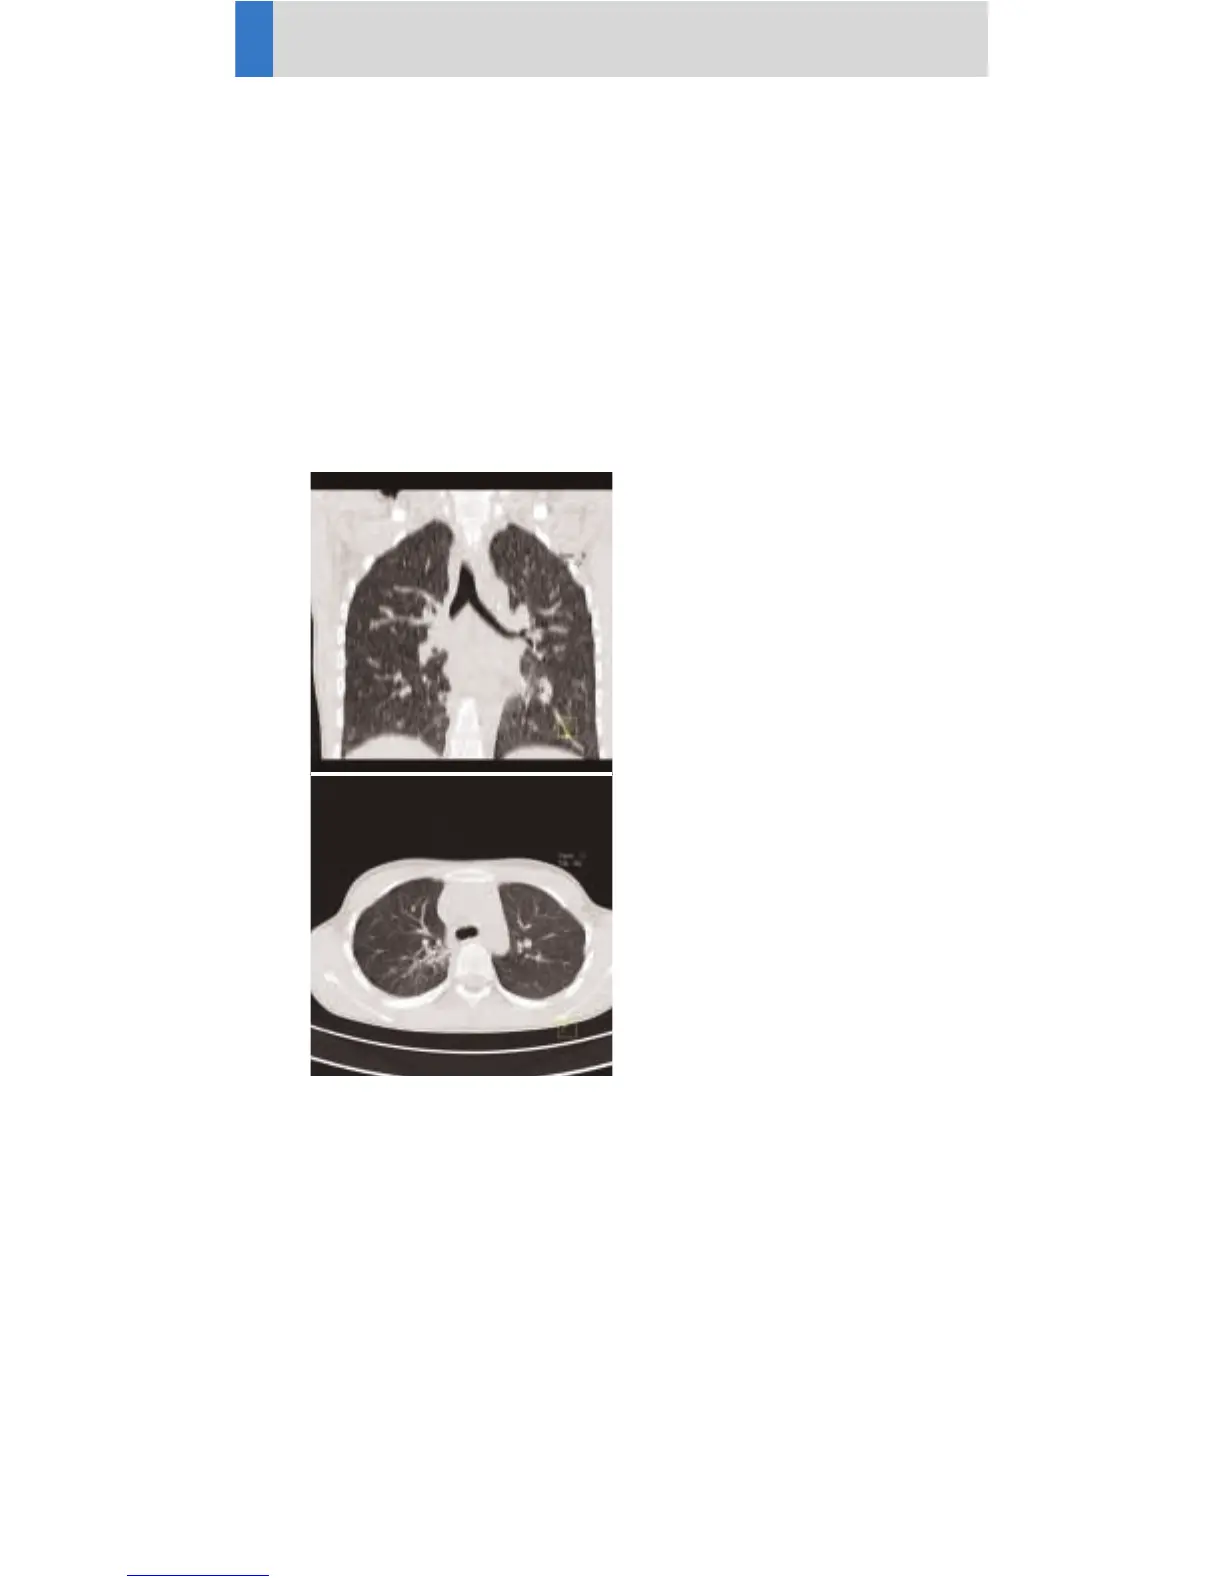

ThoraxRoutine

Indications:

Spiral mode for routine thorax studies, e. g.

pneumonia, tumors, metastases, lymphoma, vascular

abnormalities etc.

A range of 15 cm will be covered in 8.3 sec.

Children